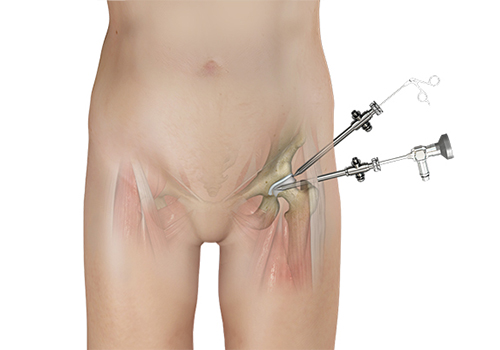

Hip arthroscopy, also referred to as keyhole or minimally invasive surgery, is a surgical procedure in which an arthroscope is inserted into your hip joint to check for any damage and repair it simultaneously.